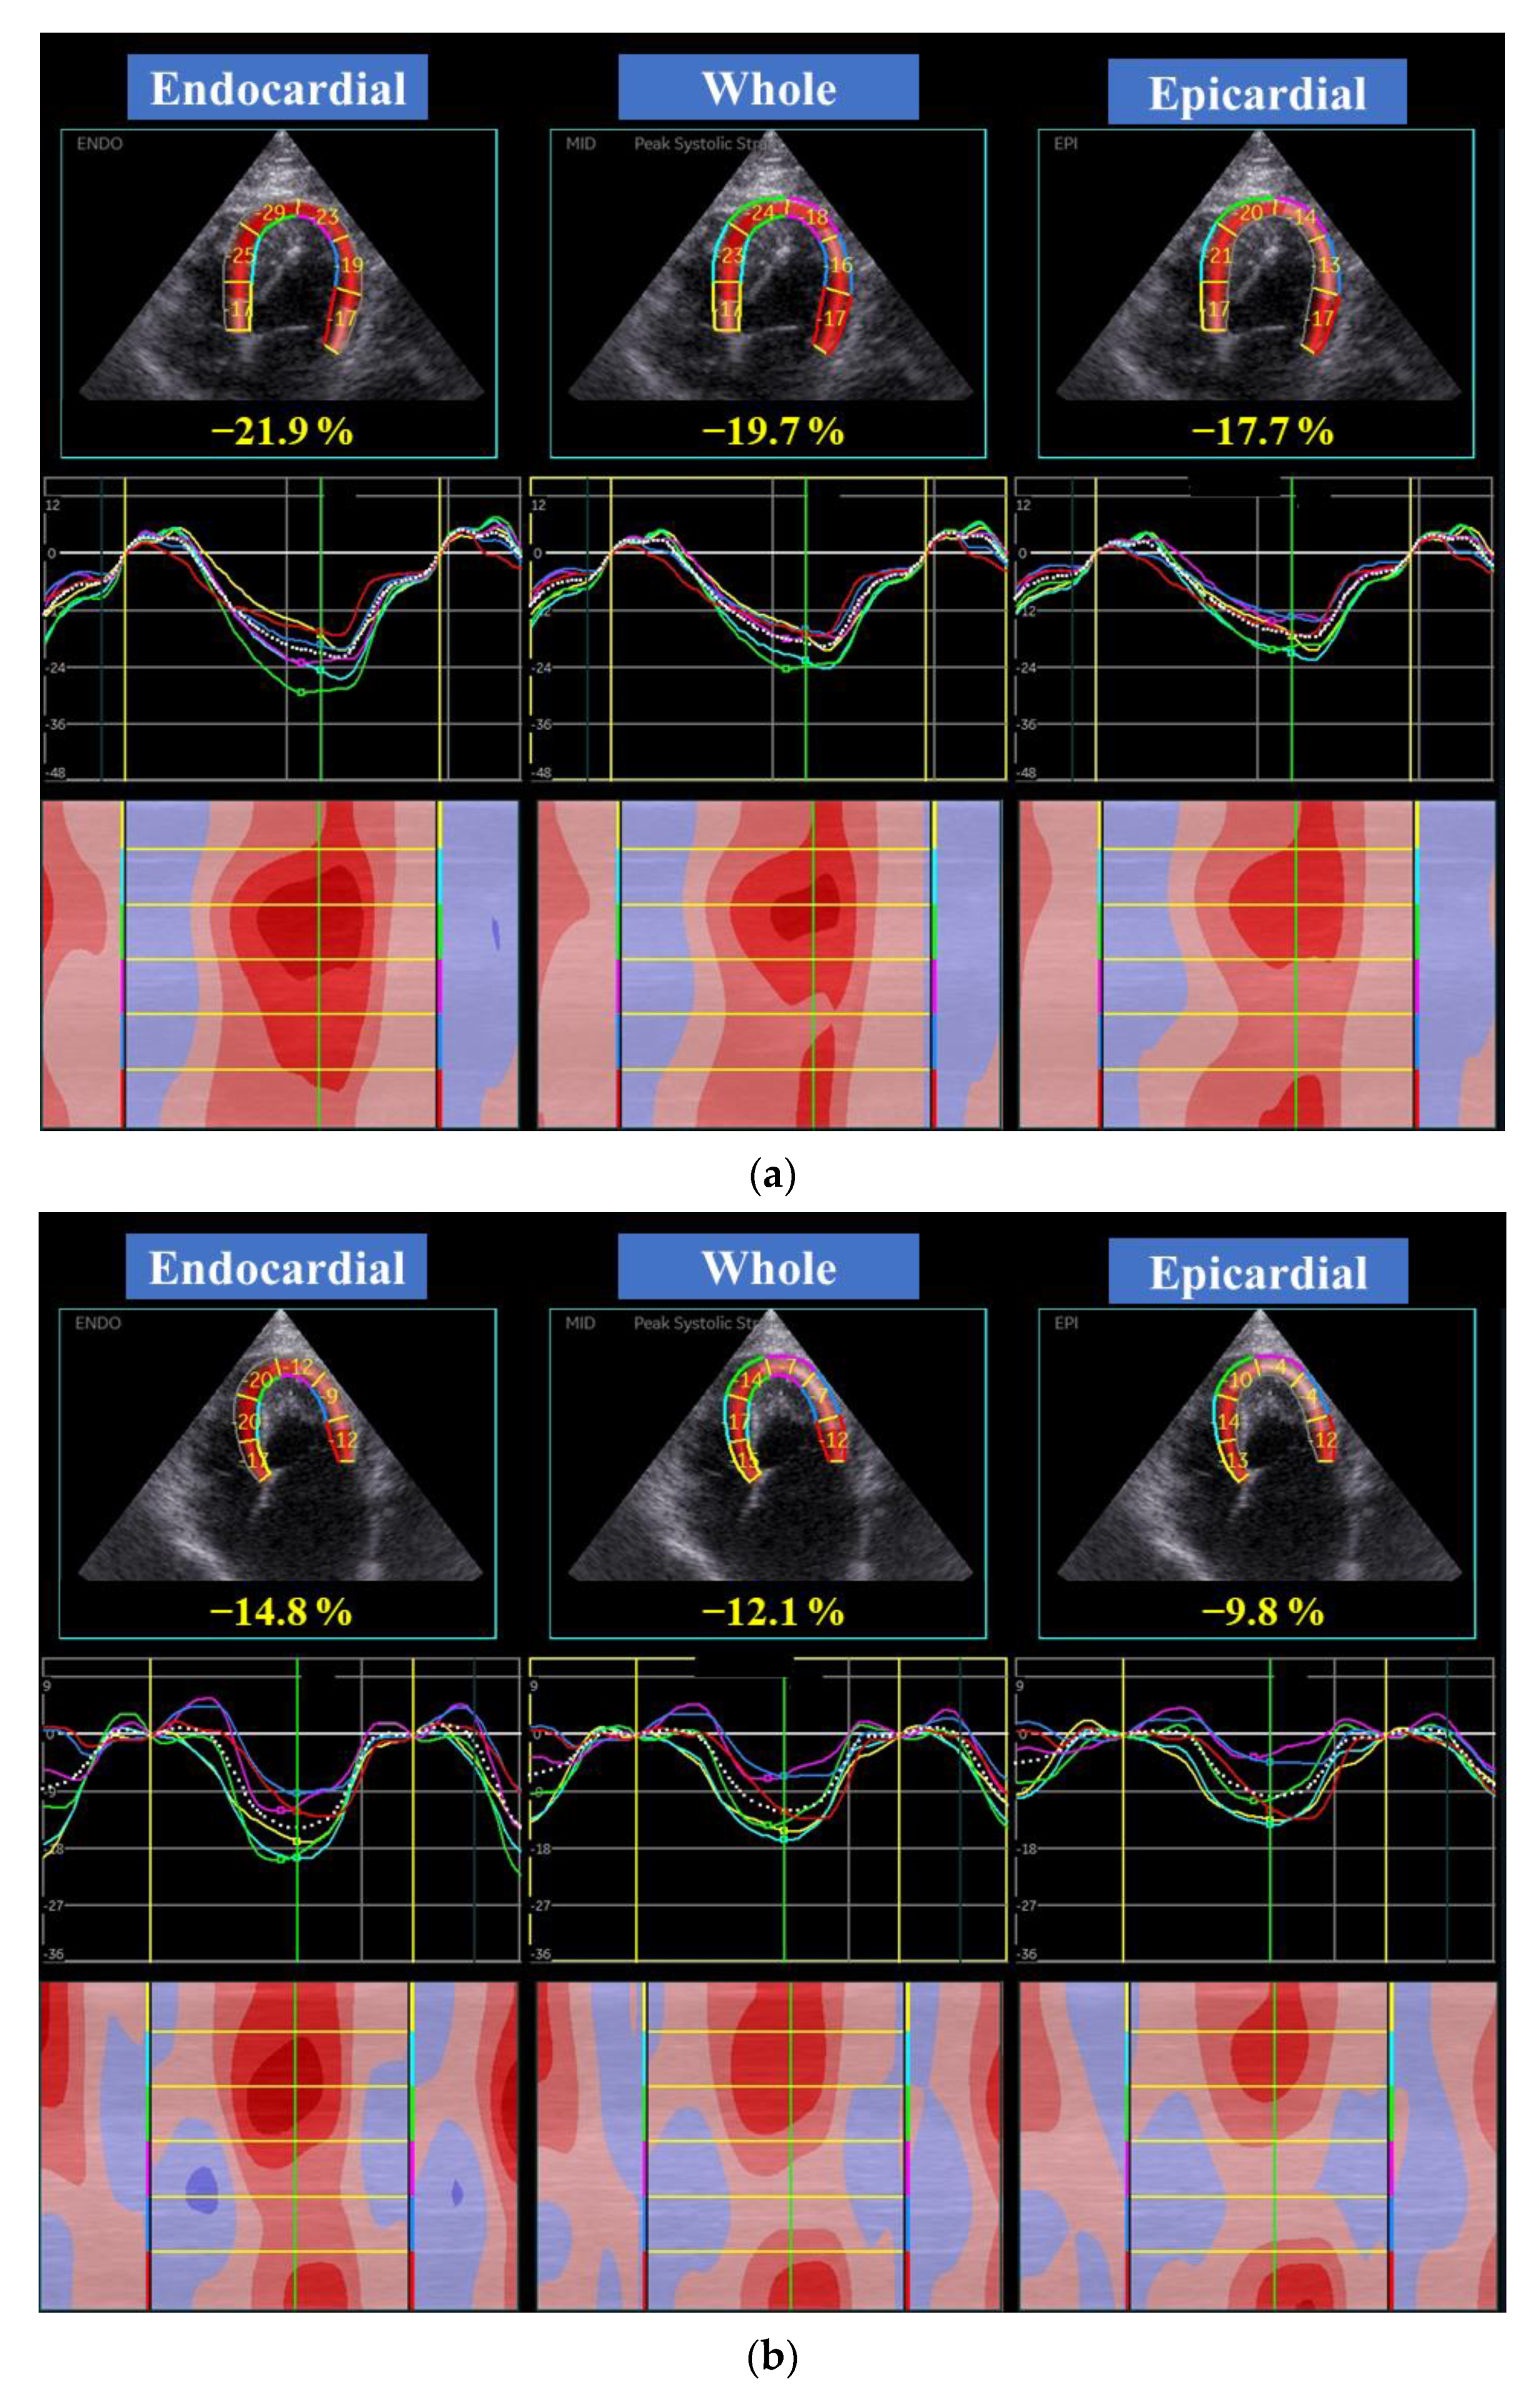

| Global LV longitudinal strain (%) | |||||||

| Whole layer | 13.4 | (11.4, 20.8) | 10 | 20.8 | (18.3, 22.6) | 15 | 0.04 |

| Endocardial layer | 16.3 | (13.6, 23.6) | 10 | 23.8 | (21.9, 25.3) | 15 | 0.08 |

| Epicardial layer | 11.8 | (9.2, 17.3) | 10 | 18.5 | (16.1, 19.8) | 15 | <0.01 |

| Endo/Epi | 1.43 | (1.34, 1.55) | 10 | 1.36 | (1.2, 1.4) | 15 | 0.03 |

| Global LV circumferential strain (%) | |||||||

| Whole layer | 17.4 | (15.4, 21.3) | 10 | 19.1 | (17.3, 23.9) | 15 | 0.09 |

| Endocardial layer | 27.7 | (25.4, 32.6) | 10 | 38.7 | (32.7, 48.3) | 15 | <0.01 |

| Epicardial layer | 10.4 | (8.5, 12.3) | 10 | 7.3 | (6.2, 9.3) | 15 | 0.14 |

| Endo/Epi | 2.73 | (2.08, 4.06) | 10 | 4.77 | (4.12, 6.50) | 15 | <0.01 |